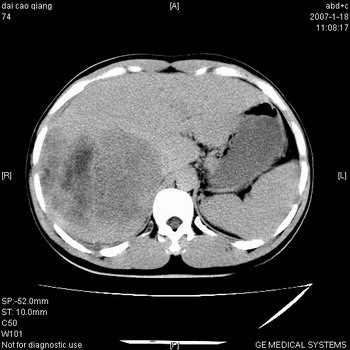

符合巨块型肝癌表现:

1、平扫低密度,增强后表现为快进快出。

3、并可见门静脉右支癌栓形成

4、可见假包膜

肝右叶巨大不均匀低密度肿块,前缘有假包膜,增强明显的呈快进快出表现,门脉右支有癌栓,病人虽然年轻但还是首先考虑肝右叶巨块形肝癌,病人血象高只能说有合并感染。不支持肝脓肿。

巨块型肝癌并门静脉右支癌栓